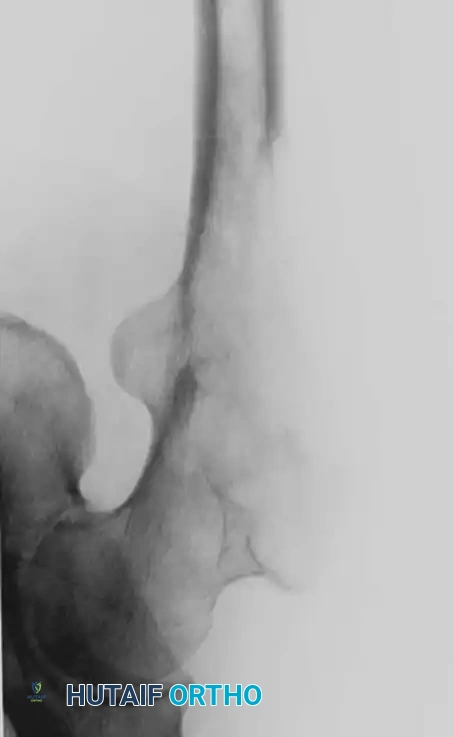

Fig. 22-24: (A, B) Anteroposterior and lateral radiographs of the proximal femur in an 82-year-old man with metastatic kidney cancer revealing multiple lytic lesions. Prophylactic fixation was canceled due to medical instability. (C) Radiograph several weeks later showing a completed pathological fracture. Surgery is now exponentially more difficult, and the patient has suffered severe morbidity.